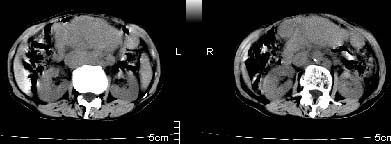

主动脉-胰腺间隙可见巨大分叶状软组织肿块影,包绕腹主动脉、腹腔干及其分支、腔静脉等大血管,增强呈无明显强化,临近脏器明显受压移位,增强示有分界。肝右叶可见局限性低密影,边缘清楚。

考虑腹膜后淋巴瘤。

影象表现:平扫,首先可见胃壁明显增厚,内外边缘清晰,外缘光滑,内边缘不归整,同时胃腔明显缩小。

再看从肠系膜根部到胰腺后主动脉及上腔静脉周围可见相连的较大的软组织肿块影,形态不规则,呈明显

的大小不等的分叶状,其中密度较均匀但其中可见条状低密度区,肿块边缘比较清晰周围的小肠受压移位

明显且堆积。

增强所见,腹腔动脉,肠系膜上动静脉被肿块包绕,结合平扫的条状低密度区恰好位于血管周围,较大的

肿块强化不明显(遗憾的是没有标上ct值)但胃壁强化的十分明显。

临床表现:老年女性:61岁.腹痛腹胀20天,查体发现患者右颈根部约3厘米类圆性包块。

影象诊断:考虑淋巴瘤待除外胃癌腹膜后淋巴结转移